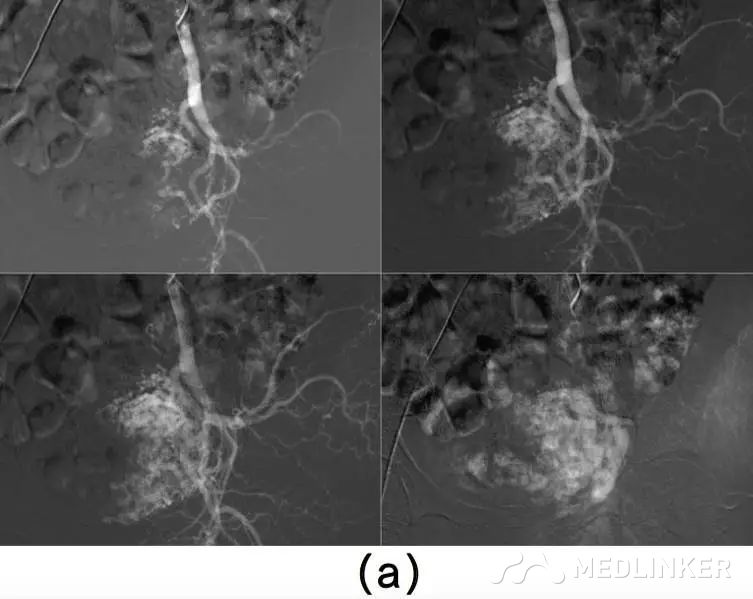

患者入院诊断:动静脉畸形。介入科会诊后行双侧子宫动脉栓塞术,栓塞材料为氰丙烯酸丁酯和碘油的混合物。该患者栓塞前后情况如图2所示。子宫动脉栓塞术后,患者未出现并发症,术后2天,患者出院,血hCG降至1766mIU/mL。术后1个月复查超声,未见血流,且受损范围缩小至61∗46∗52mm(77cm3)(图3),血hCG<0.5mIU/mL。  图2(a)右/左髂内子宫动脉造影术示:轻度扩张的子宫动脉显影浑浊,子宫内见多血管性肿块;(b)双侧子宫动脉栓塞术后图像   图3(a)2个月后的阴式超声示::受损范围缩小至61∗46∗52mm(77cm3);(b)多普勒彩超未见血流              根据年龄、生育要求、病变位置及范围大小选择不同的治疗方案,AVM主要的治疗方法是子宫切除和子宫动脉栓塞。育龄期有生育要求的子宫动静脉瘘患者首选治疗方法是子宫动脉栓塞,但是其远期的安全性尚存争议,而且行子宫动脉栓塞术后,妊娠的孕妇发生胎位异常、早产、产后出血及剖宫产的风险增大。        一些学者认为保守治疗适合无症状的AVM患者;还有学者认为出血少的AVM患者可以用甲基麦角新碱、促性腺激素释放激素类似物、达那唑等治疗。总之,目前对无症状的子宫动静脉瘘的治疗暂无统一的共识。        总之,子宫动静脉瘘是比较罕见且危险的临床疾病。通常,这种疾病常见于既往发生过自然流产的年轻女性,我们应该牢记行人工流产术(吸宮术)的患者,术后可能会继发子宫动静脉瘘,同时应该注意该病与其他疾病的鉴别。